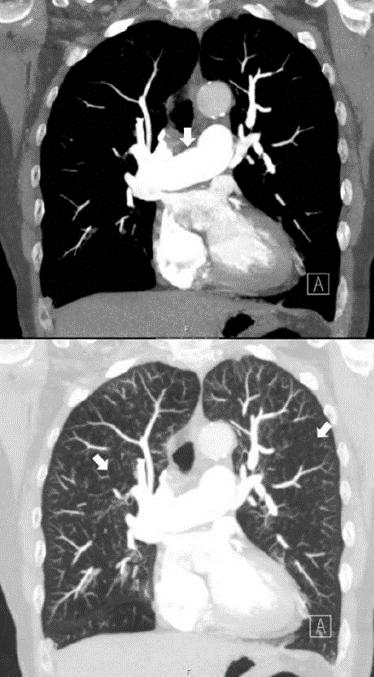

Vad ser du på bilden?

DT thorax utförd med intravenös kontrast på lungembolifrågeställning. Två koronara snitt i höjd med truncus pulmonalis; den övre bilden i mediastinumfönster och den nedre i lungfönster.

Notera hur breddökad truncus pulmonalis (indikerad med pil på den övre bilden) är i förhållande till arcus aortae, vilket är ett tydligt tecken på högt tryck i lungkretsloppet. Notera också generellt fläckvis varierande attenuering (kärlen syns inte, svart bild liksom, kan innebära luft som fastnar i experium) i lungparenkymet (indikerat med pilar i nedre bilden), ett mönster som kallas mosaik pattern. Ett litet infiltrat ses lateralt-basalt i höger lunga.

Vad säger oss fyndet av ”mosaik pattern i inspiration” och ”air-trapping” på DT?

CTEPH kan ge denna bilden med pulmonell hypertension